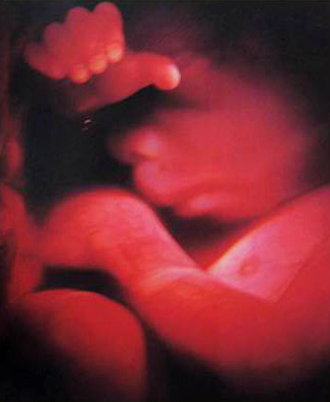

- 10주 이전

- 질 초음파 (1회/2주)

- 산모종합검사 (풍진, 간염, 매독, 에이즈, 빈혈, 혈액형, 갑상선, 소변검사)

- 10주 이후

- 초기 정밀 초음파

- 복부 초음파